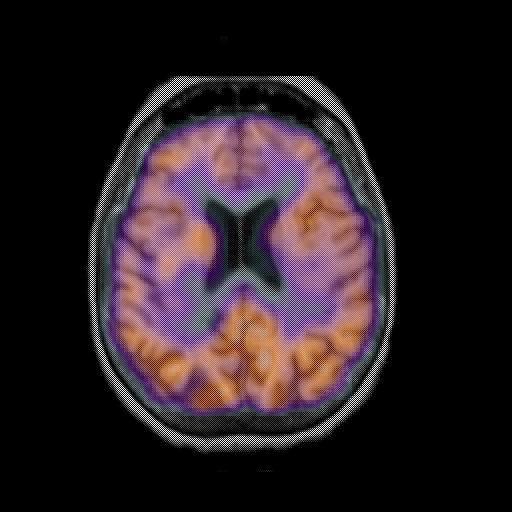

overlay: Slice 34

Slice 34